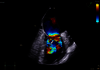

Maîtriser les flux de travail exigeants

Découvrez des performances et une productivité extraordinaire

Avec une qualité d'image exceptionnelle qui accentue les contours, augmente la clarté et améliore la définition entre les structures, Vivid Pioneer offre une base optimale pour que l'IA délivre tout son potentiel. Simplifiez et rationalisez les mesures et la quantification en toute confiance. Obtenez des résultats cohérents et fiables pour tous les utilisateurs.